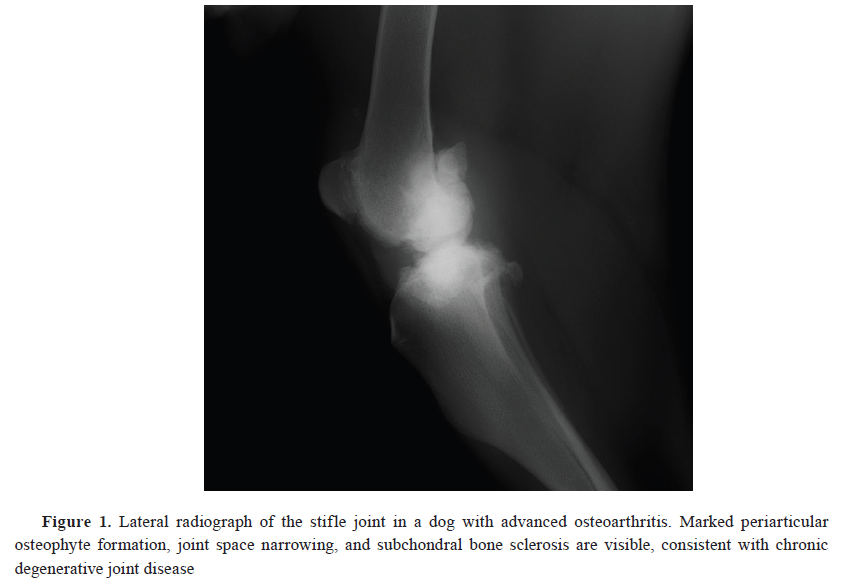

12). Radiographic imaging was used to confirm the presence and severity of OA in the affected joints (

Fig. 1). Following diagnosis, dogs confirmed to have OA and associated pain were recommended and offered a comprehensive, multimodal treatment plan in consultation with their owners, adhering to ethical standards of veterinary care.